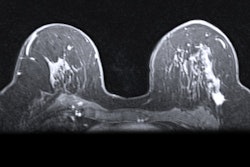

Images show breast cancer in two women at baseline multiparametric MRI. (A) Image shows axial delayed-phase dynamic contrast-enhanced MRI scan in a 51-year-old woman with luminal B no special type carcinoma in the left breast 240 seconds after gadolinium chelate injection. (B) Image shows axial T2-weighted image in the same woman as in (A). At core biopsy, the lesion was considered as HER2 low. The lesion was correctly classified by the radiomic signature (0.87 ≥ threshold). (C) Image shows axial delayed-phase dynamic contrast-enhanced MRI scan in a 43-year-old woman with luminal B no special type carcinoma in the right breast 240 seconds after gadolinium chelate injection. (D) Image shows axial T2-weighted image in the same woman as in (C). At core biopsy, the lesion was considered as HER2 zero. The lesion was correctly classified by the radiomic signature (0.45 < threshold). Images and caption courtesy of the RSNA.

Images show breast cancer in two women at baseline multiparametric MRI. (A) Image shows axial delayed-phase dynamic contrast-enhanced MRI scan in a 51-year-old woman with luminal B no special type carcinoma in the left breast 240 seconds after gadolinium chelate injection. (B) Image shows axial T2-weighted image in the same woman as in (A). At core biopsy, the lesion was considered as HER2 low. The lesion was correctly classified by the radiomic signature (0.87 ≥ threshold). (C) Image shows axial delayed-phase dynamic contrast-enhanced MRI scan in a 43-year-old woman with luminal B no special type carcinoma in the right breast 240 seconds after gadolinium chelate injection. (D) Image shows axial T2-weighted image in the same woman as in (C). At core biopsy, the lesion was considered as HER2 zero. The lesion was correctly classified by the radiomic signature (0.45 < threshold). Images and caption courtesy of the RSNA.The training set included 208 women with an average age of 53 years from one center, while the external test set included 131 patients with an average age of 54 years from a second center.